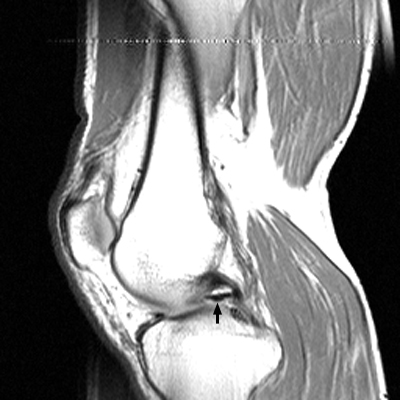

Diagnosis:Bucket-handle tear of the menisci Discussion:The displaced fragment of a bucket handle tear of the meniscus can move medially to lie within the intercondylar notch. The fragment-in-notch sign is defined as a band like area of low signal intensity within the intercondylar notch, not appearing on the same slice as the PCL. The sign, when identified, can be valuable in picking up a bucket handle tear of the meniscus. References: